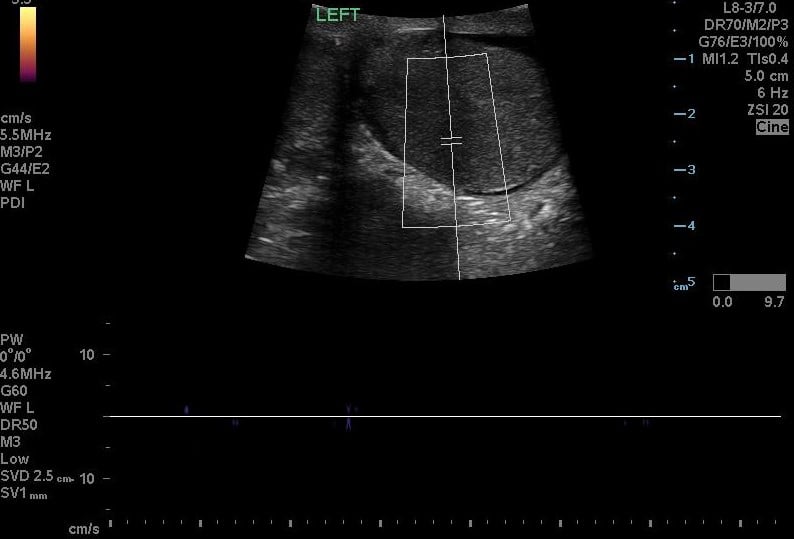

Testicular Torsion

Brief narrative description of case

You are working overnight in a single coverage ED when a 15-year-old male presents with his mom for lower abdominal pain. The patient was playing basketball 3 hours ago and suddenly felt severe lower abdominal pain. No trauma to the abdomen. No history of STIs. No dysuria or hematuria. Sexually active with one female partner and does not use condoms. No drugs or alcohol. No prior surgeries. Tylenol and Motrin did not work at home. The pain has now been persistent for the past 5 hours, and progressively worsening. Learners are expected to obtain a social and sexual history from the teen and identify testicular torsion on exam and using ultrasound. Learners must perform manual detorsion techniques and consult urology for definitive management.